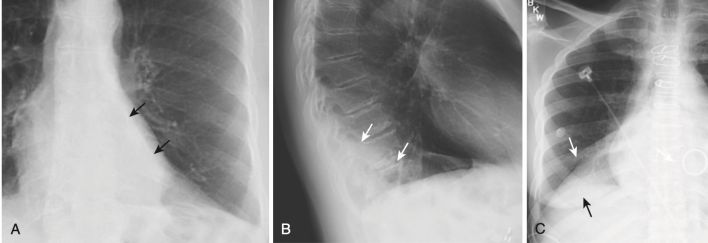

Xẹp phổi thùy dưới (Hình 12, A và Hình 12, B)

- Trên phim X quang thẳng:

- Cả thùy dưới bên phải và bên trái xẹp xuống tạo thành mật độ hình tam giác kéo dài từ đỉnh của rốn phổi đến đáy của nó ở phần trong của nửa cơ hoành bị ảnh hưởng.

- Có sự nâng lên của nửa cơ hoành ở bên bị ảnh hưởng.

- Tim có thể lệch về phía mất thể tích.

- Có sự dịch chuyển xuống dưới của rãnh liên thùy lớn (xem Hình 12, C).

- Trên phim X quang nghiêng:

- Có cả sự dịch chuyển xuống dưới và ra sau của rãnh liên thùy lớn cho đến khi thùy dưới bị xẹp hoàn toàn tạo thành mật độ hình tam giác nhỏ ở góc sườn hoành sau (xem Hình 12, B).

- Ở bệnh nhân nặng, xẹp phổi thường xảy ra nhất ở thùy dưới bên trái.

- Luôn kiểm tra nửa cơ hoành trái để chắc chắn rằng có thể quan sát được toàn bộ cơ hoành trái qua bóng tim vì xẹp phổi thùy dưới bên trái sẽ biểu hiện bằng sự biến mất (bóng bờ) của toàn bộ hoặc một phần của cơ hoành trái (xem Hình 12, A) .